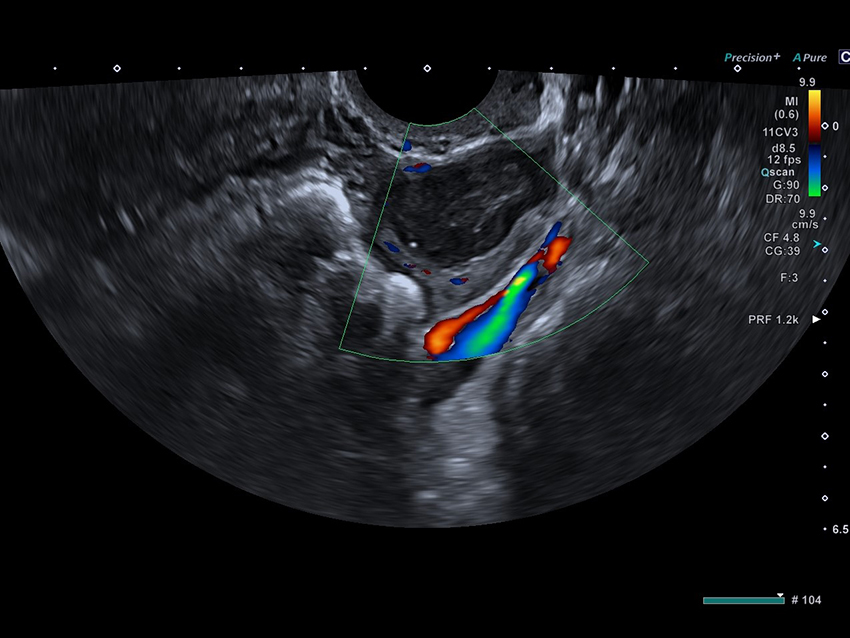

SlowflowHD per la visualizzazione dei microflussi

Valutazioni ginecologiche di precisione

Analisi morfologica e funzionale